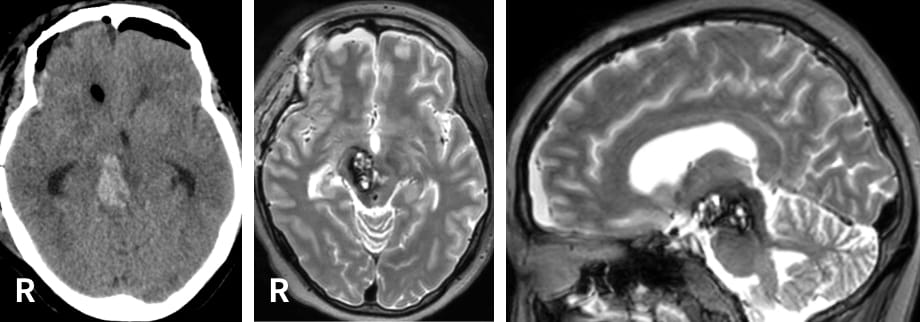

右下肢の感覚障害で発症された、左頭頂葉、長径約8 cmのグリオーマ(乏突起膠腫 Grade 3)。最も前方の嚢胞により中心溝が強く前方へ圧迫されていた。運動神経モニタリングの下で手術が行われ、ほぼ全摘出された。術前画像にて乏突起膠腫が疑われていたこともあり、摘出腔に抗がん剤ウエハースが留置された。

術前

術後